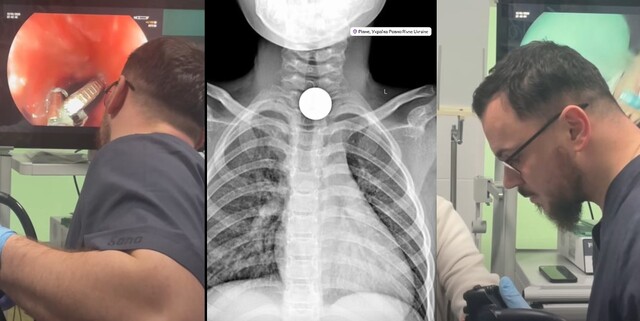

Угорські гроші дістав хірург із горла дитини в м. Рівне: лікар Красько – попереджає (ФОТО/ВІДЕО)

10 Форинтів

Уже не перший рік лікар-ендоскопіст Максим Красько відомий у Рівному тим, що він рятує дітей, дістаючи із їхніх стравоходів різні несподівані речі.

Цього разу дитячий хірург повідомив про нову «знахідку».

І навіть виклав ще й спеціальне відео в рилз:

Під час обстеження рентген-знімок показав, що монета перебувала у верхньому відділі стравоходу, в ділянці входу до нього.